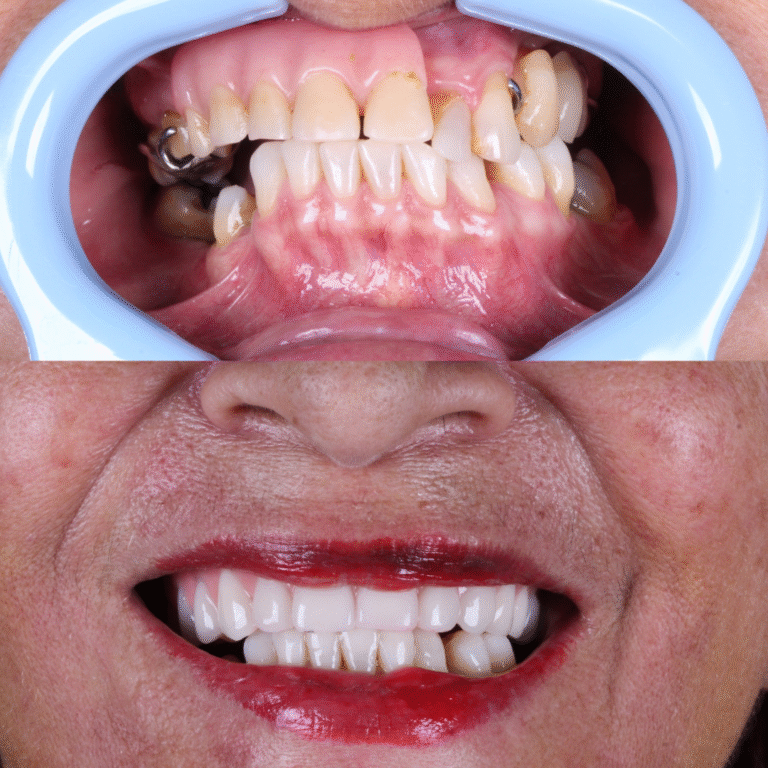

O All-on-Four é um protocolo de implantes dentários que utiliza apenas 4 implantes para fixar uma prótese total, substituindo todos os dentes da arcada.

Diferente de técnicas convencionais, não exige enxertos ósseos na maioria dos casos, tornando o tratamento mais rápido e confortável.

Mais do que estética, uma vida nova!

Perderam todos os dentes ou têm dentes comprometidos e desejam uma solução fixa e duradoura.

Desejam um sorriso natural, bonito, saudável e estável. Sem medo de se relacionar ou falar em público.

Em muitos casos, é possível instalar dentes fixos no mesmo dia da cirurgia. Isso significa que o paciente recupera a estética do sorriso e a função mastigatória muito mais rápido do que em técnicas convencionais.